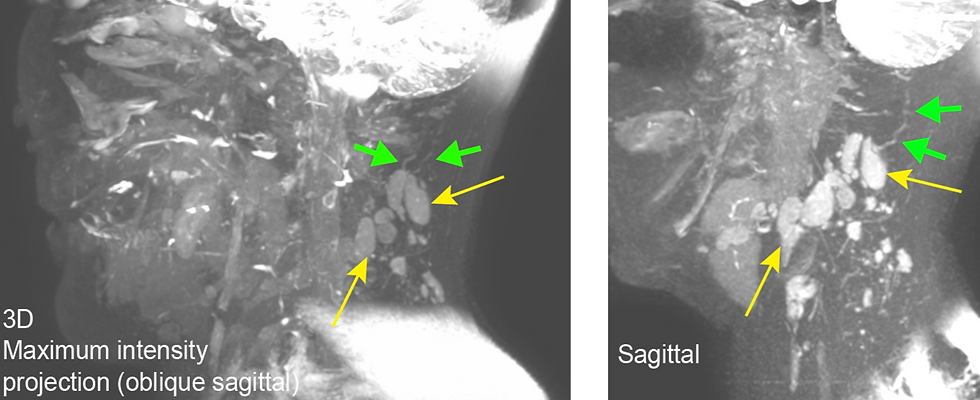

Since approximately 2013, we have worked on developing methods to assess lymphatic collector structure and function before and after cancer therapies. Specifically, BCRL is a chronic, debilitating disease caused by lymphatic flow obstruction and lymphedema secondary to mastectomy with radiation therapy has been reported to occur in 20-30% of breast cancer survivors following these therapies. However, owing to a lack of methodology for sensitively identifying lymphatic system compromise, there are important gaps in our knowledge regarding which patients are at highest risk and how and when therapies should be applied to minimize impairment. In this work, novel and noninvasive magnetic resonance imaging approaches for measuring lymphatic dysfunction are applied to improve procedures for preventing, predicting, and treating BCRL.

Our initial trials in BCRL have ended and are open for data analysis only. Ongoing extensions of this work focus on evaluating lymphatic tissue structure and function in the neck, and specifically, how such cervical lymphatic changes relate to retention of cerebral peptides in patients with neurodegenerative proteinopathies.